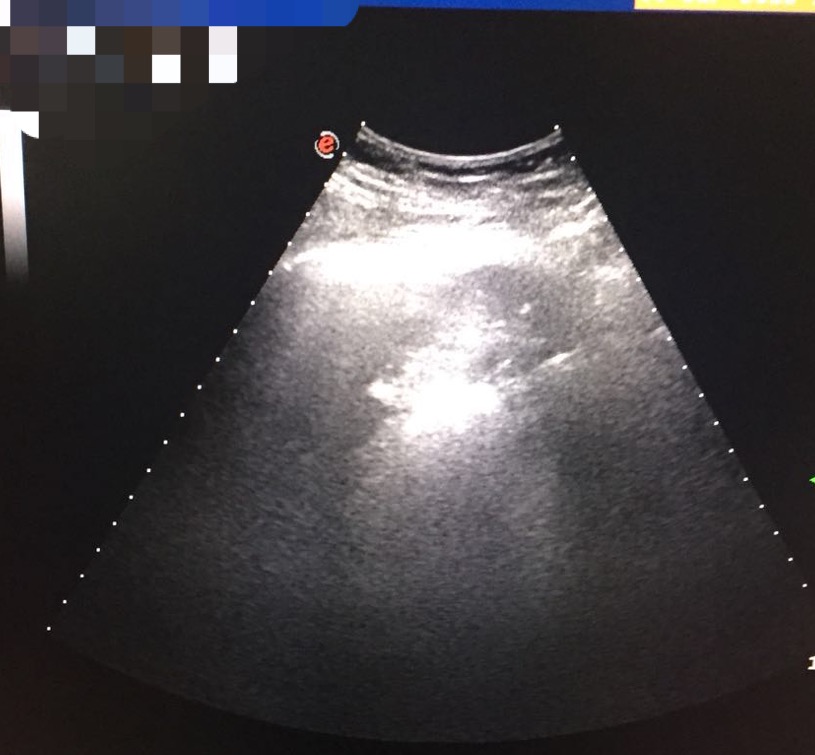

消融术中B超影像